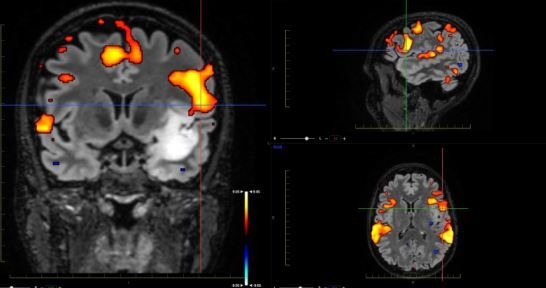

Αφού έγινε ένας ενδελεχής έλεγχος με μαγνητική δεσμιδογραφία (ώστε να δούμε από που ακριβώς περνάνε τα σημαντικά νευρικά δεμάτια) καθώς επίσης και λειτουργική μαγνητική (ώστε να δούμε πόσο κοντά στα κέντρα της ομιλίας ήταν ο όγκος), αποφασίστηκε η διενέργεια κρανιοτομίας με την ασθενή ξύπνια (awake craniotomy), με τη χρήση διεγχειρητικού υπερήχου,και διεγχειρητικού νευροφυσιολογικού ελέγχου (neuromonitoring).